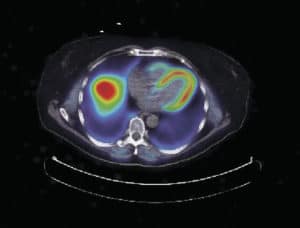

然而,Carpentier教授使用非侵入性PET(正电子发射断层摄影术)成像的方法克服了这些局限性。PET是一种灵敏的成像技术,可以检测微小(皮摩尔)示踪剂浓度。Carpentier教授进行了一项研究,健康受试者口服放射性标记示踪剂FTHA (14-R, s -f -氟-6-硫-十七烷酸),这是一种长链脂肪酸类似物。随后进行了6个多小时的连续全身PET采集。在此期间,所有示踪剂的运动被记录为三维图像,以突出全身示踪剂的划分。从本质上说,这使得DFA在不同组织和器官中的脂肪储存得以测量。结果表明,健康男性肝脏和心脏的DFA含量较高。然而,骨骼肌和皮下脂肪组织储存的DFA含量相对较低。

Carpentier教授还研究了DFA在棕色脂肪组织(BAT)中的分配。BAT的功能是通过生热调节体温——通过氧化脂肪储存产生热量来提高体温。受试者口服FTHA并暴露于18°C的低温环境中。PET成像结果证实BAT在冷曝光时确实摄取DFA。然而,BAT组织每体积的DFA分配比肝脏低83%,比心脏低55%,仅占全身DFA清除的0.3%。

该团队还探索了糖尿病前期和肥胖(血糖水平正常)受试者组织体积中器官特异性DFA的分配。有趣的是,研究结果支持了一个观点,即糖尿病前期状态会导致无效的脂肪DFA组织存储,这与肥胖密切相关。在精瘦器官分配方面,肝脏或骨骼肌的DFA存储在健康、肥胖和糖尿病前期个体之间没有差异。然而,Carpentier教授发现,糖尿病前期患者的心脏DFA摄入量明显更高。在健康和肥胖个体中,2-3%的dfa储存在心脏中。然而,在糖尿病前期个体中,这一比例上升到4%,这可能导致严重的心脏并发症,如左心室功能障碍和潜在的心力衰竭。尽管这一发现令人担忧,但卡彭迪埃教授表示,通过改变生活方式,适度减少体脂,可以逆转DFA流向心脏的通道。受这个有希望的结果的启发,Carpentier教授和他的同事们正在探索防止T2D发展的其他机制。